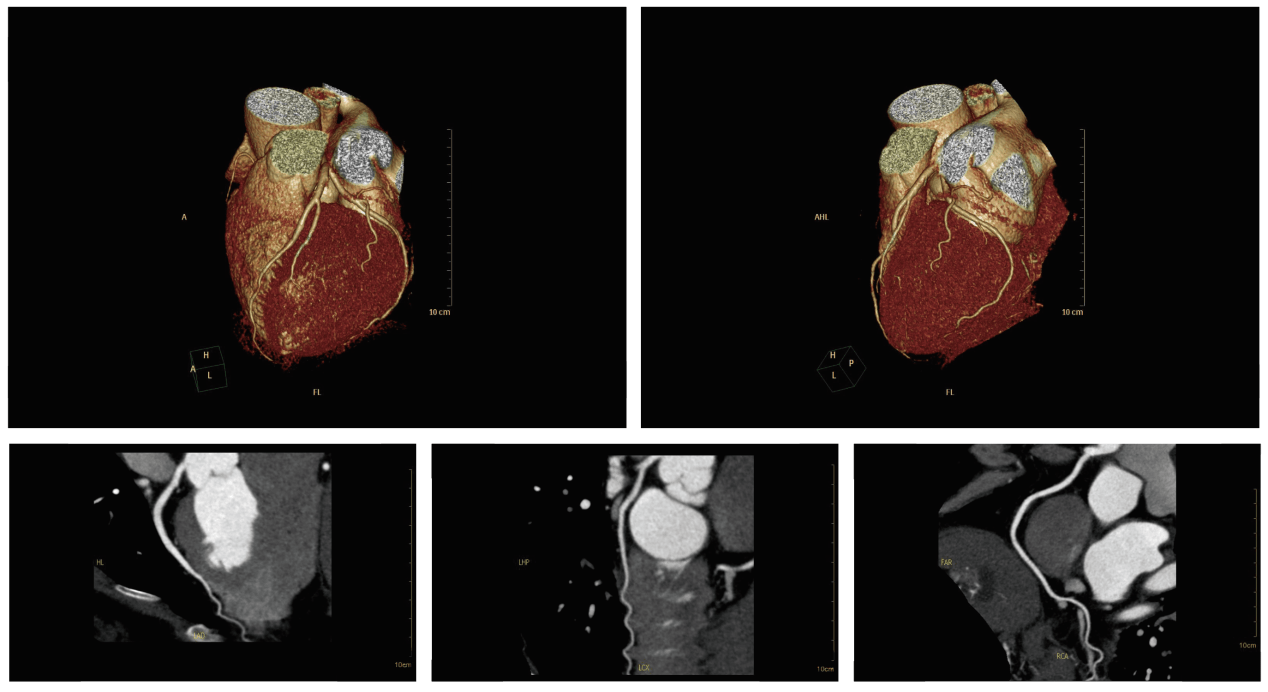

开影医疗CT新品Precision 128 Max 精密断层能谱CT具有发明专利精密断层技术,能够实现0.3125mm层厚采集高清晰度结构成像,具有超高速度扫描0.298秒/圈、时间分辨率高达29.8ms,能够进行快速心脏成像和动态相位成像,同时拥有高分离度能谱成像,全面开拓了CT诊断的新领域。

超高速旋转0.298秒/圈:Precision 128 Max CT采用业内先进的机械结构,得到高速稳定的旋转,实现全身快速扫描、心脏和组织动态成像。基于业内领先的硬件平台,提供0.298秒/圈的超高速旋转,时间分辨率达到29.8ms,能够适应快速心率的心脏成像,同时配备心脏自动扇区选择和心电编辑技术,大幅度提高心律波动和心律失常病检查的成功率,快速扫描能够在5秒钟内完成心脏扫描。

此外,开影医疗自主研发医学影像处理系统CIW具有强大的后处理能力,具备2D/3D可视化、虚拟内窥镜、脑灌注分析、能谱成像分析、血管分析、心脏浏览、冠脉分析等诸多高级临床应用,功能全面稳定、流程高效易用、维护简单并持续改进,满足放射医师的更多需求。